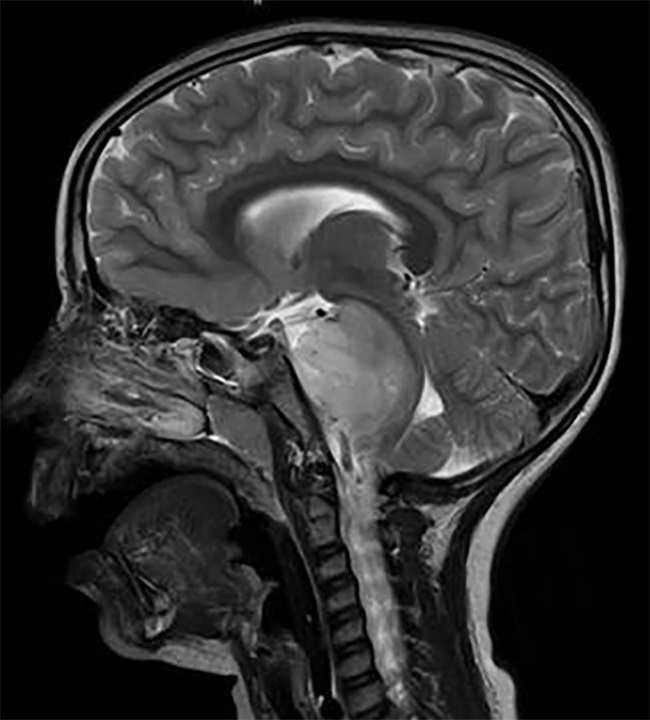

AVM的診斷是通過計算機斷層掃描(CT)、磁共振成像(MRI)和腦血管造影,其中包括x射線(x射線)成像,然后注射造影劑。簡單地說,造影劑被注射到一根導管中,導管插入病人的股動脈,然后通過頸內(nèi)動脈到達大腦。拍攝的影像顯示了AVM的局部位置。這些影像學檢查很重要,因為除了顯示AVM的位置外,它們還可以用來確定AVM的原始大小、治療后的大小變化,以及AVM是否出血或未破裂。通常,AVM 病灶的評估是通過一種名為Spetzler-Martin (SM)分級量表的評分方法進行的,該方法有助于評估手術(shù)死亡風險和嚴重不良反應(SAEs)。SM分級量表考慮到了: